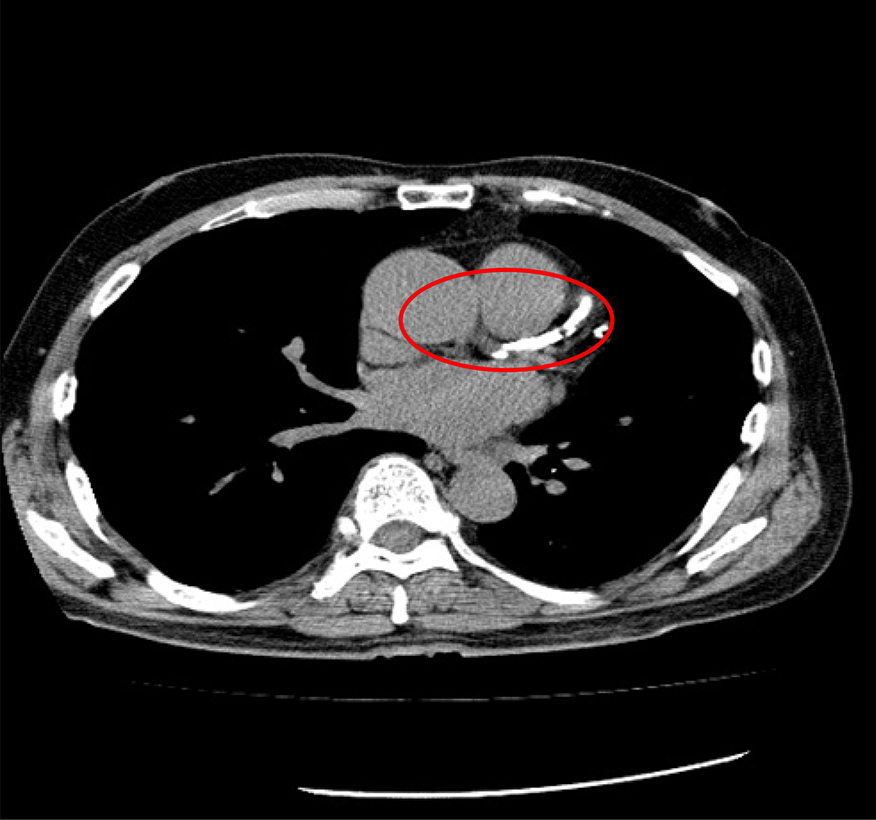

石灰化スコアCT

心臓を栄養する血管である冠動脈の石灰化を測定するCT検査です。

胸部CTより少ない被ばく線量で造影剤を使わず、比較的簡便に心筋梗塞や狭心症のリスクを調べられる検査です。

冠動脈の石灰化は動脈硬化が進行し、血管の壁にカルシウムが沈着した状態です。石灰化が多いほど動脈硬化が進み心筋梗塞や狭心症のリスクが高くなります。

石灰化スコアCTで血管の状態を調べてみましょう。

石灰化が認められない血管

石灰化が認められる血管